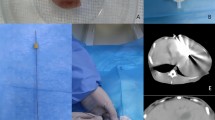

PET/MRI Protocol and Region-of-Interest (ROI) Placement

All patients followed a standardized PET/MRI protocol by using a hybrid PET/MRI scanner (Biograph mMR, Siemens Healthcare, Erlangen, Germany) as reported in our previous study19. In addition to the standard PET protocol and MR attenuation correction sequence, the MRI protocol also included three-dimensional (3D) Dixon sequence and a series of breath-hold dynamic contrast enhancement (DCE) sequence using 3D fat-saturated VIBE (volumetric interpolated breath-hold examination) at the corticomedullary, nephrographic and excretory phases with delay times of 25 s, 75 s, and 180 s, respectively (with the detailed parameters of 3D sequences provided in the Supplementary Table S1). In order to investigate the potential links between intratumoral angiogenic expressions and image features, a team of experienced radiologists, nuclear medicine specialists, and surgeons collaborated pre-operatively to place several ROIs in different parts of tumors on PET/MRI. Pre-contrast and three post-contrast sets of DCE images were then evaluated together. The post-contrast set exhibiting the signal changes was finally chosen, overlaid with PET, and visually evaluated. Several ROIs (~1 cm diameter) were defined in the regions with FDG uptake, where each defined ROI had internal uniform contrast enhancement. These defined ROIs were transferred to the operation room for tissue sampling after total nephrectomy under supervision of a board certified radiologist19. Figure 1 shows two illustrative cases of excretory phases of DCE images for ROI placement.

(a) A ROI was placed in the well-enhancing part in left renal clear cell carcinoma in a 37-year-old female patient. The total microvascular density was 313.08/mm2. (b) A ROI was placed in left renal cell carcinoma in a 46-year-old female patient. This part was only slightly enhanced. The total microvascular density was 54.74/mm2.